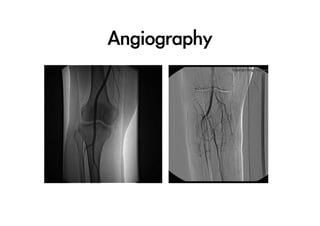

Angiography

Revascularization

•  評估下肢血管:PE,Doppler,

血管攝影